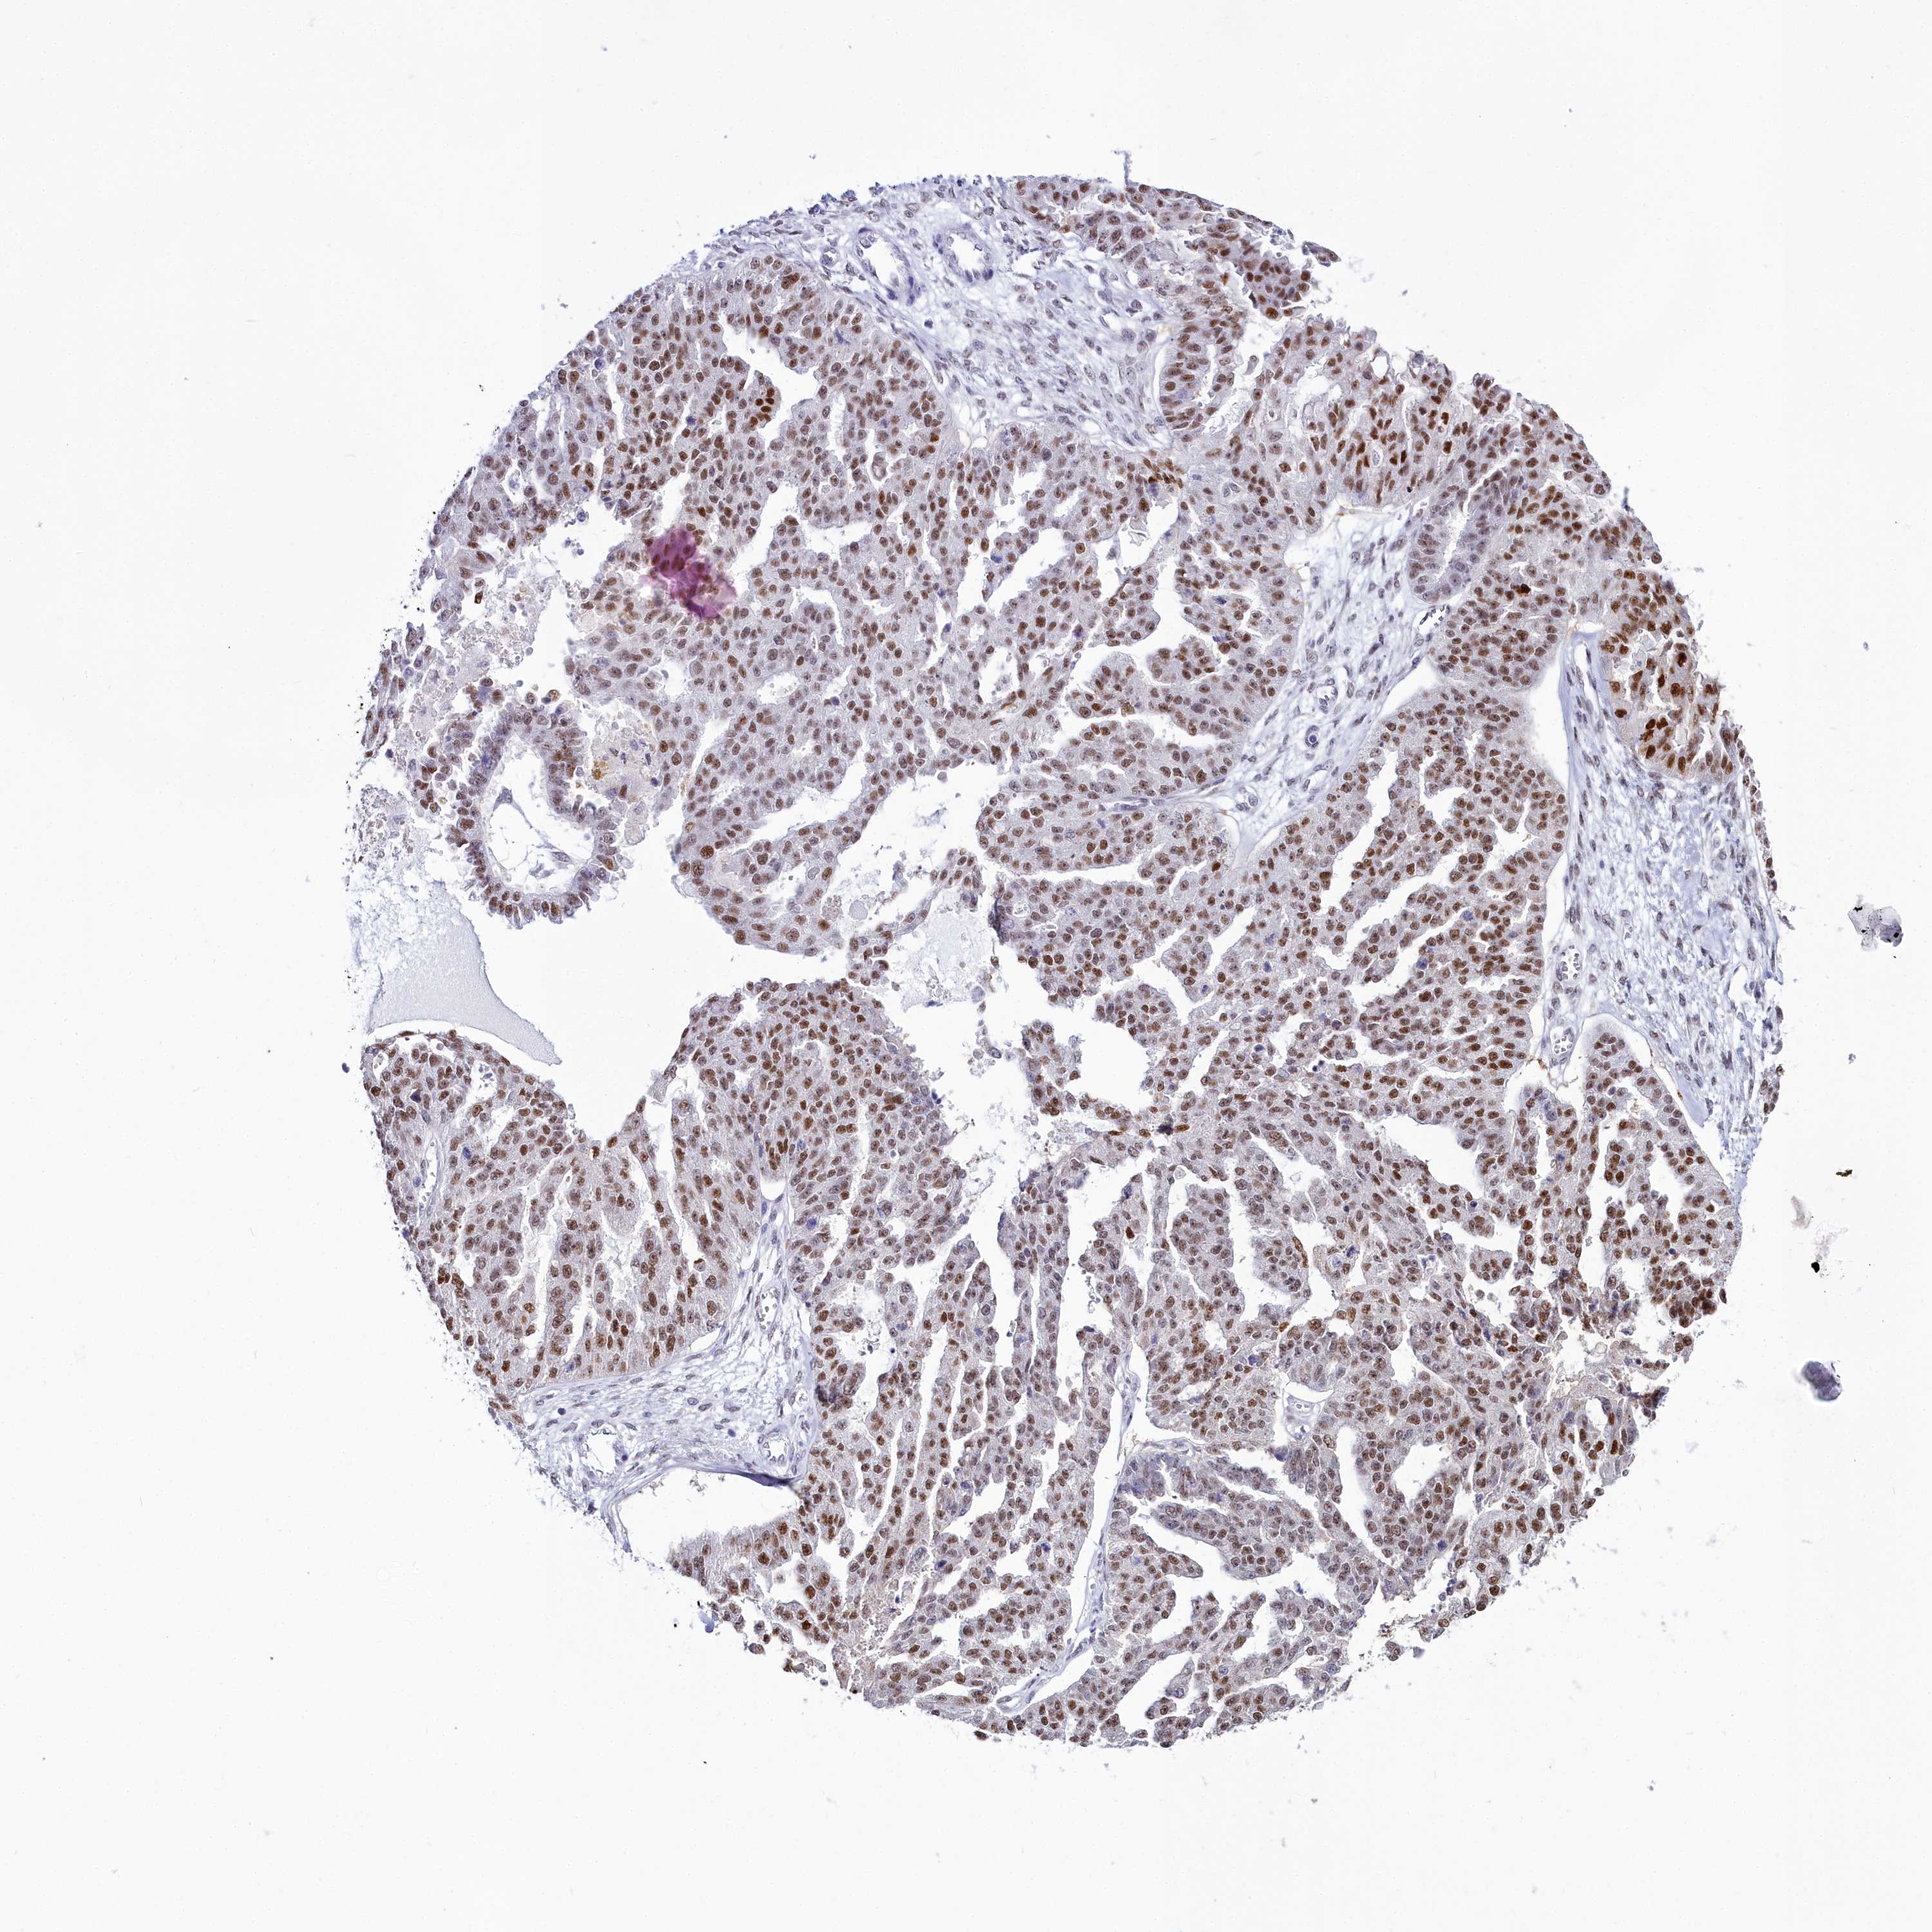

OVARIAN CANCER - Protein expressioni

A mouse-over function shows sample information and annotation data. Click on an image to view it in a full screen mode. Samples can be filtered based on level of antibody staining by selecting one or several of the following categories: high, medium, low and not detected. The assay and annotation is described here.

Note that samples used for immunohistochemistry by the Human Protein Atlas do not correspond to samples in the TCGA dataset.

Antibody stainingi

Antibody staining in the annotated cell types in the current human tissue is reported as not detected, low, medium, or high, based on conventional immunohistochemistry profiling in selected tissues. This score is based on the combination of the staining intensity and fraction of stained cells.

Each image is clickable and will lead to virtual microscopy that enables deeper exploration of all samples and also displays staining intensity scores, fraction scores and subcellular localization as well as patient and tissue information for each sample.

Antibody HPA043258

Antibody HPA043621

Staining

High

Medium

Low

Not detected

Intensity

Strong

Moderate

Weak

Negative

Quantity

>75%

75%-25%

<25%

None

Location

Nuclear

Cytoplasmic/membranous

Cytoplasmic/membranous,nuclear

Cystadenocarcinoma, serous, NOS

Carcinoma, NOS

Cystadenocarcinoma, mucinous, NOS

Carcinoma, endometroid